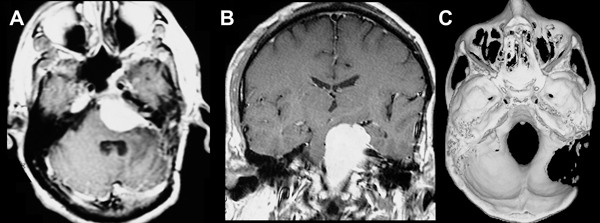

Figura 1. A) RMN, ponderación T1, con gadolinio, corte axial. Se observa la persistencia del meningioma petroclival izquierdo y las huellas de los procedimientos quirúrgicos previos. B) RMN, ponderación T1, con gadolinio, corte coronal. Se observa la persistencia del meningioma petroclival izquierdo después de los procedimientos quirúrgicos previos. C) Tomografía computada, corte axial, ventana ósea, reconstrucción 3D. Se observa la craniectomía suboccipital lateral izquierda, retrosigmoidea con extensión temporal, utilizada en las 4 ocasiones quirúrgicas previas.